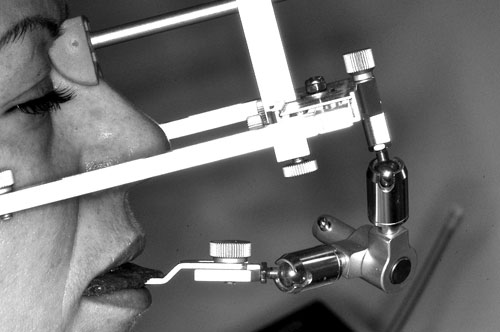

Se realiza un montaje en articulador semi ajustable, mediante la técnica de arco facial convencional para el maxilar superior, y mediante relajación con Laminillas de Long para el inferior. No satisfechos de la certeza del primer montaje, construimos en el un Jig de Lucia que dejamos toda una noche en boca para remontar el inferior al día siguiente a primera hora.

FIGURA 6 Laminillas de Long

Jig de Lucia FIGURA 9